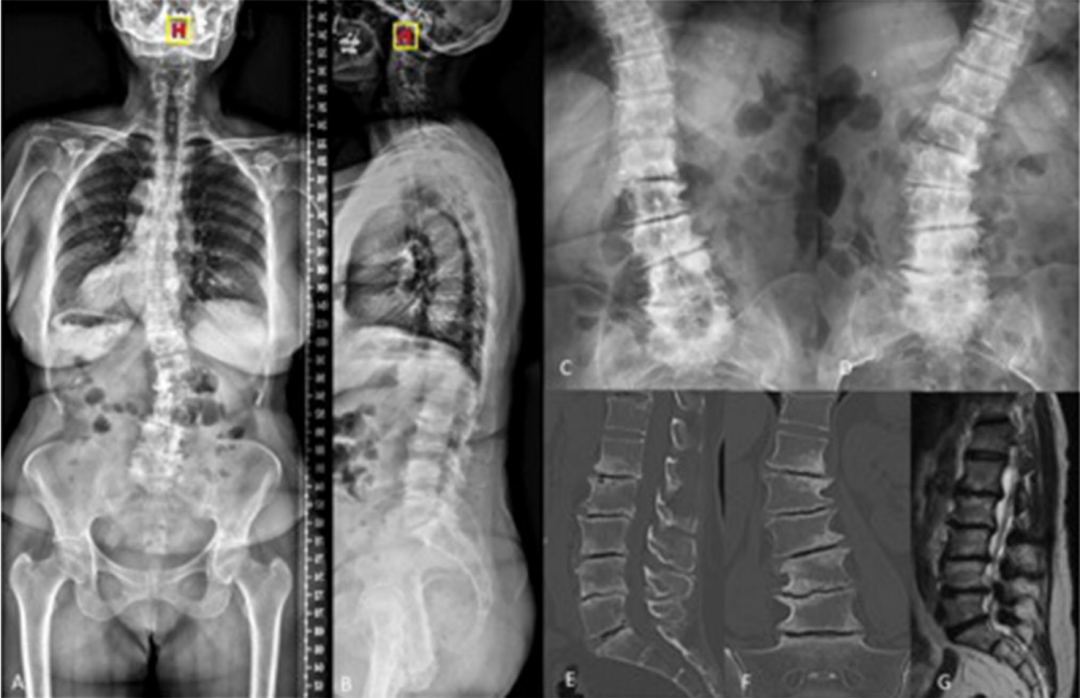

图: 术前影响资料可见退行性侧凸伴多节段椎间盘真空征

图: A: 俯卧位,髋关节伸展,以增加腰椎前凸和椎间盘间隙; B: 经皮透视下放置Jamshidi针; C: 在肌电图监护下穿刺并注射; D: 缓慢注射骨水泥

图: 椎弓根外入路(经安全三角,类似于椎间盘造影入路)

图: 椎弓根入路

图: 术后情况

图: 与典型病例相似的另一退变性侧凸患者,术前存在手风琴现象,经多节段PCD术后冠状位得到10°的纠正且恢复部分腰椎前凸